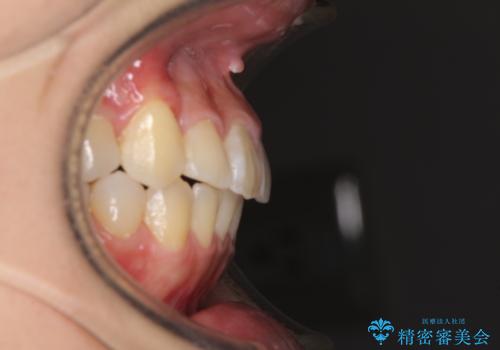

- 前歯のでこぼこと乳歯が残るほどの八重歯を気にして来院された患者様です。

非抜歯にてワイヤー矯正にて治療することとしました。(ただし、親知らずと乳歯は抜歯)

犬歯は歯根が太く長いため、移動には時間を要します。しかし、犬歯は機能面から考えて残すことを選択したいため、長期間をかけて治療を行うこととしました。